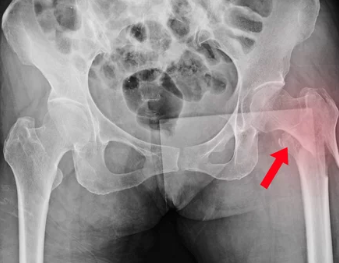

고관절 탈구는 엉덩이뼈(골반)와 허벅지뼈(대퇴골)가 연결된 관절에서 대퇴골두가 제자리에서 이탈하는 상태를 의미합니다. 이는 보통 강한 외부 충격이나 관절의 퇴행성 변화로 인해 발생합니다.

- 후방 탈구(Posterior Dislocation):

- 가장 흔한 유형(전체 탈구의 90%)

- 대퇴골두가 골반 뒷부분으로 빠지면서 다리가 짧아지고 안쪽으로 돌아감

- 넘어질 때 엉덩이로 강하게 충격을 받을 경우 발생

- X-ray 또는 CT 촬영 후 신경 손상 여부 확인